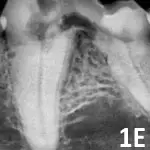

Stage 4: Extensive hard tissue loss. Most of the tooth loses integrity. In stage 4A (See Figure 1D), the crown and root are equally affected; in stage 4B (See Figure 1E), the crown is more severely affected than the root; in stage 4C (See Figure 1F), the root is more severely affected than the crown.

A dental radiograph shows the roots of a canine tooth, highlighting the surrounding bone structure and any potential periodontal disease. The image reveals the clarity of the root canal and the condition of the alveolar bone.

Figure 1E

Mandibular first molar affected by stage 4B tooth resorption.